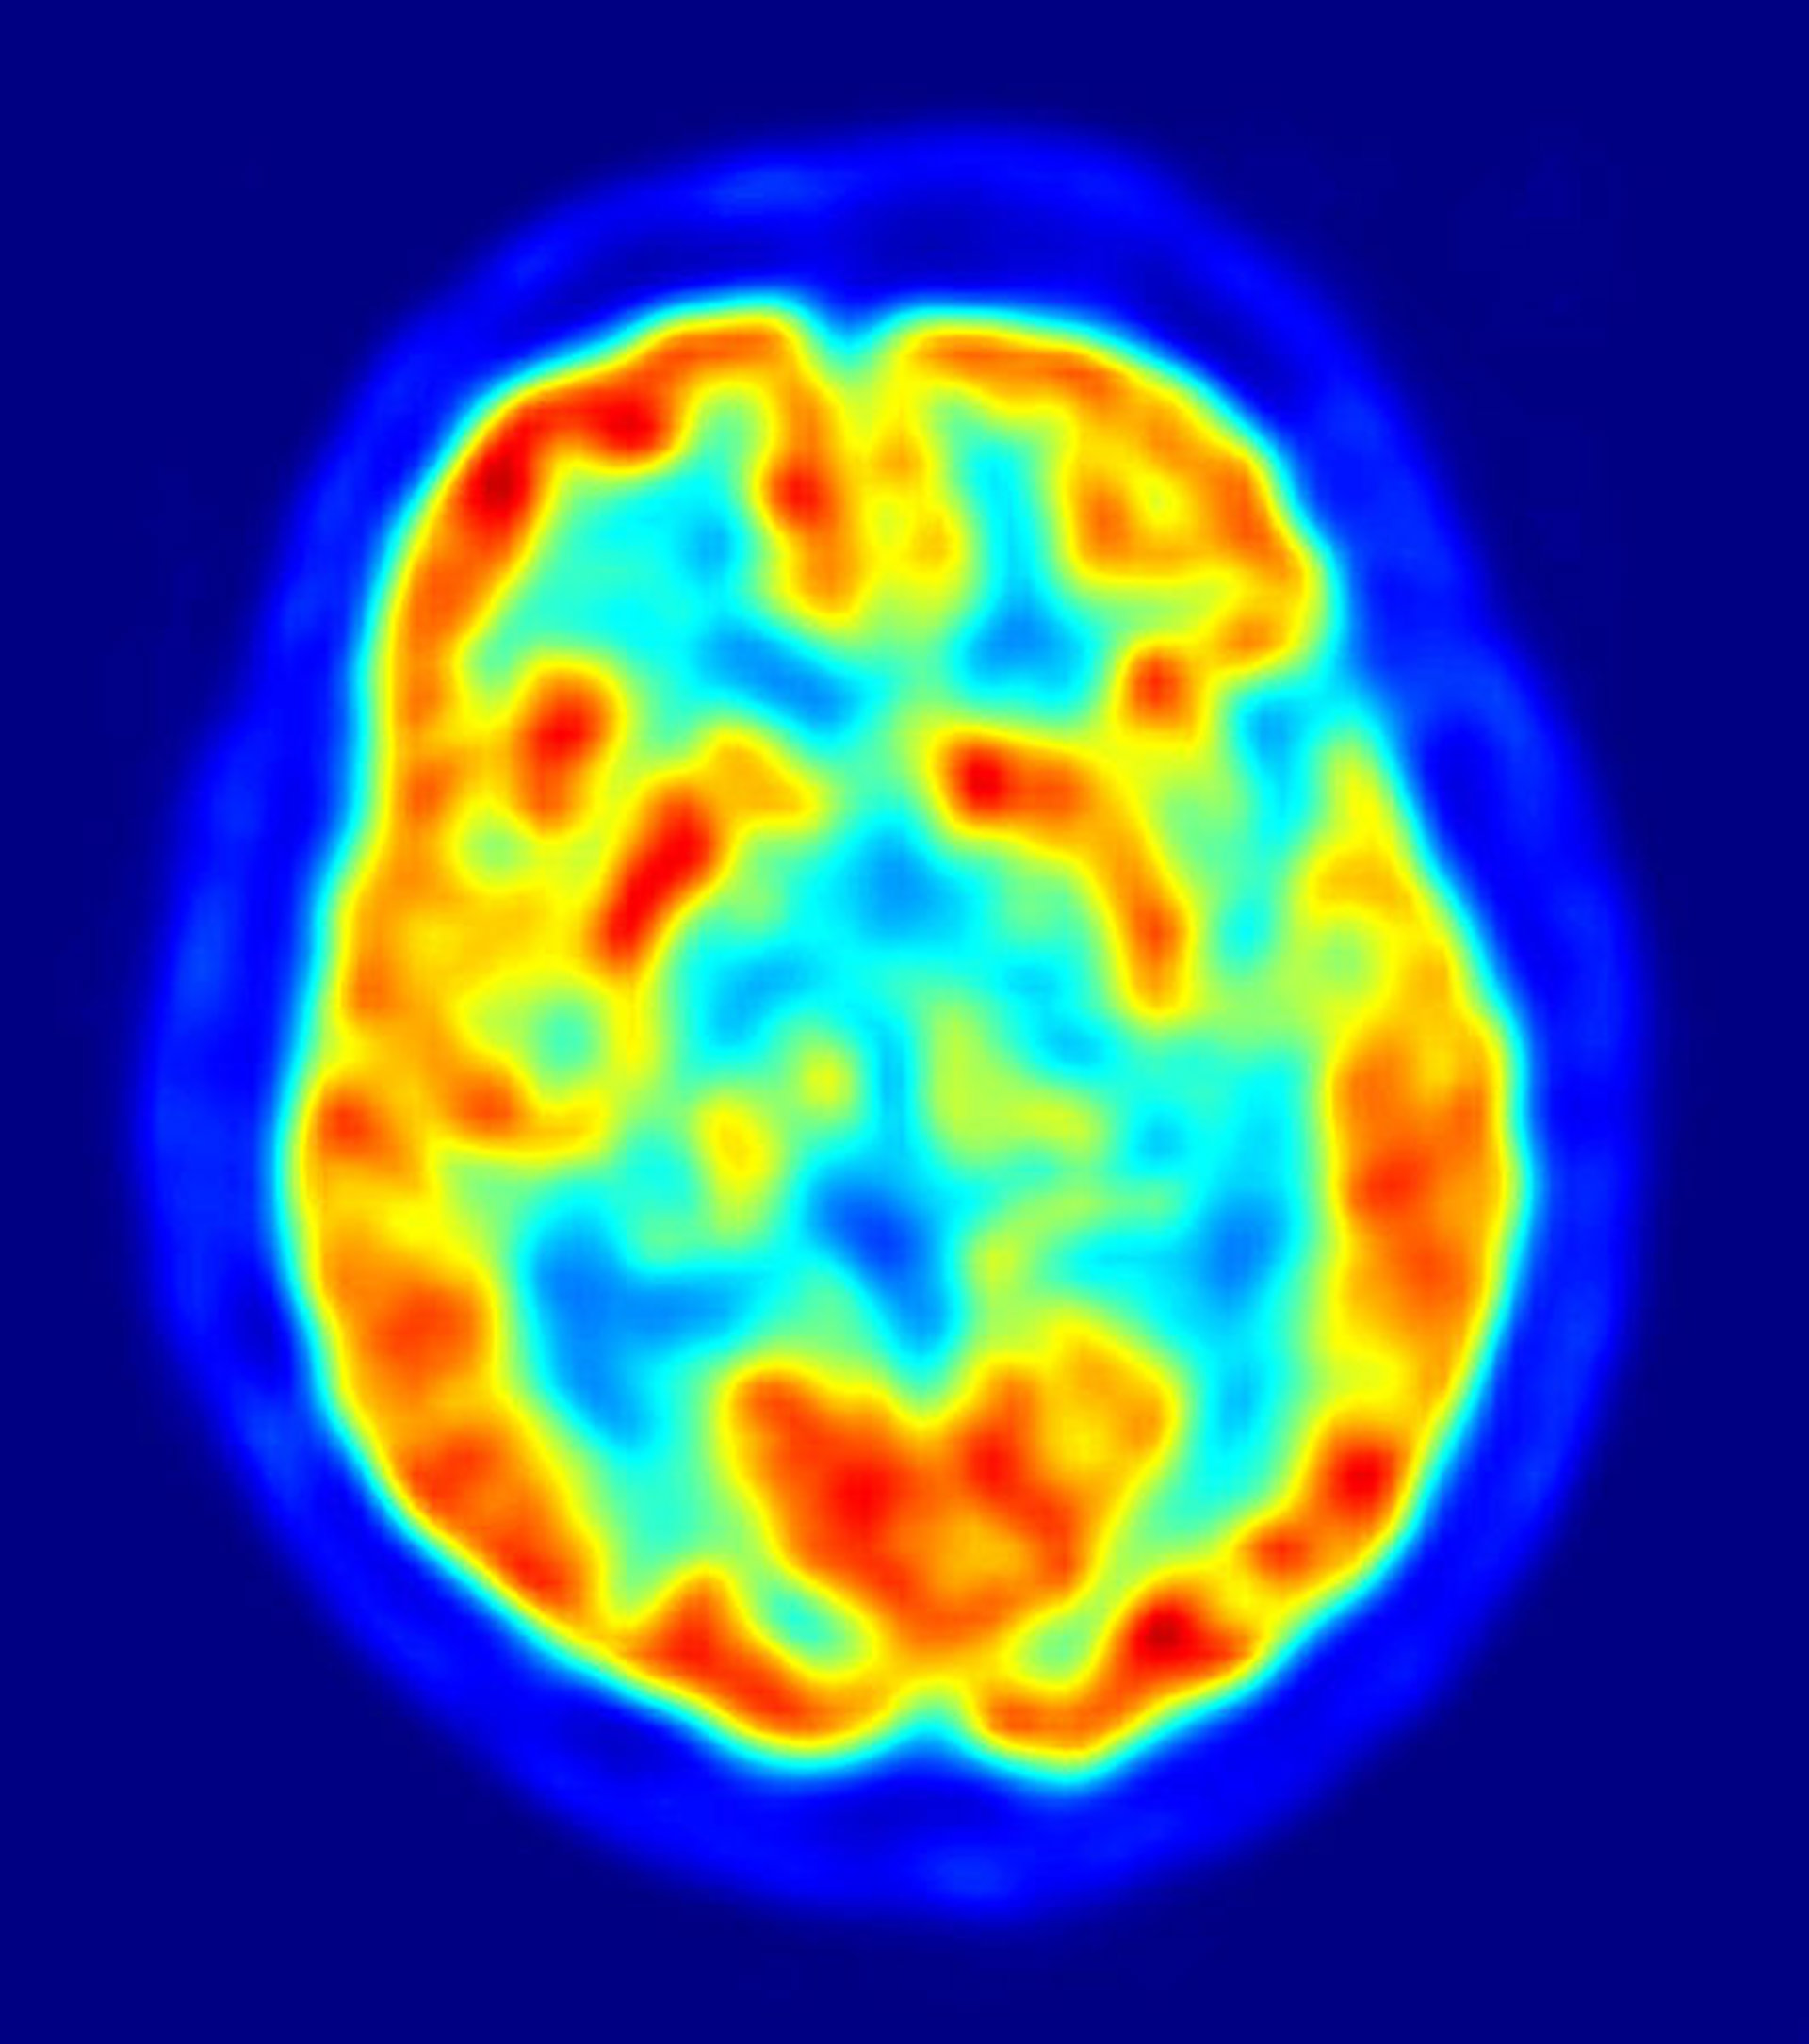

cerebro, alzheimer

Científicos del Centro de Investigación en Imagen Clínica de la Universidad de Washington, en Estados Unidos, han mostrado en el 57 Encuentro Anual SNM, que se celebra en Salt Lake City hasta este miércoles, 9 de junio, sus progresos en el uso de imágenes PET para seguir las etapas tempranas de la enfermedad de Alzheimer. Este hallazgo podría llevar al descubrimiento de medidas preventivas que beneficiarán a millones de pacientes que sufren este desorden neurodegenerativo crónico.

En uno de los pocos estudios longitudinales realizados a gran escala sobre este fenómeno, los científicos usaron una tomografía por emisión de positrones (PET, por sus siglas en inglés) para documentar los cambios que se producen durante la acumulación de beta-amiloides, que forman placas en los tejidos neuronales de los pacientes a los que se les diagnostica Alzheimer.

El PET y otras técnicas de imagen molecular ayudan a los investigadores a entender el inicio de la patología para determinar el mejor tratamiento para cada paciente, incluso antes de que aparezcan síntomas como la pérdida de memoria, las dificultades para pensar o la habilidad para realizar tareas simples. Según Mintun, "con este tipo de investigaciones, los médicos podrán recomendar el tratamiento antes de que se den daños irreversibles en el cerebro del afectado".

Un total de 129 personas, con edades entre los 45 y los 86 años y sin síntomas de padecer un desorden cognitivo, participaron en este estudio. Se sometieron a escáneres con PET en un periodo de cinco años, usando el Pittsburgh Compound-B (11C-PIB), un agente de imagen PET que muestra los beta-amiloides en el cerebro.